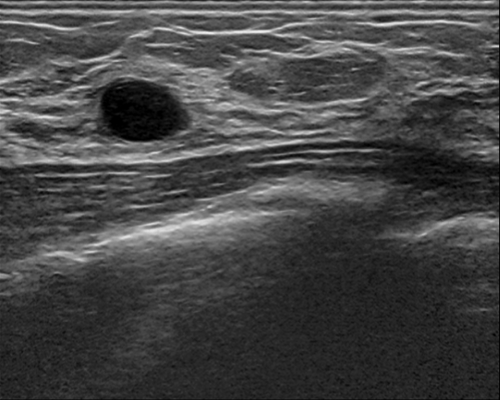

For segmentation, we employ the zero-shot method MedCLIP-SAMv2 [koleilat2024medclip, koleilat2024medclipsamv2]. It works by computing activation maps from a pre-trained CLIP model, and using them as query for the Segment Anything Model (SAM) [kirillov2023segment]. Activation maps are computed using Multi-Modal Information Bottleneck Attribution (M2IB) [wang2023visual], using a target image and a query prompt. Here, we aim at improving the quality of the activation maps on different concepts by leveraging KT. This, in turn, should result in a higher accuracy of the final segmentation. We target four different segmentation tasks: lung nodules segmentation on CT images (UnitoChest), pneumothorax segmentation on CXR images (SIIM Pneumothorax), breast nodule segmentation on ultrasound images (UDIAT), and glioma segmentation in MRIs (BraTS23).

The overall results across all segmentation tasks are presented in Tab. 7. The captions used for inversion are reported in the supplementary material. To compute the M2IB activation maps on the fine-tuned models, we employ descriptive prompts as suggested in [koleilat2024medclipsamv2]. The prompts are reported in Tab. 7 as P1 to P4 for each task. We also report reference results of MedCLIP-SAMv2 on each task. Compared to the original setting of MedCLIP-SAMv2, lung nodules and lung pneumothorax are completely novel concepts. There is also a slight difference in the brain glioma class compared to the original brain tumor task, explained in the supplementary file. We employ three metrics to assess the segmentation quality, namely the Dice-Sørensen Coefficient (DSC), Normalized Surface Distance (NSD), and Intersection over Union (IoU). We report results with different values of fine-tuning learning rate. We can observe an increase in segmentation metrics across all tasks, notably in breast ultrasound (NSD 59.44% to 61.56%) and brain MRIs (NSD 20.97% to 22.26%). For lung nodules and pneumothorax, the improvement is less pronounced, probably because the novelty of the task makes improving more difficult in the MedCLIP-SAM setting. We report some visual examples on breast tumor segmentation in Fig. 5, showcasing the improvements of KT.

Results of knowledge transfer on MedCLIP-SAMv2 with different values of learning rate are shown in Tab. 14. We report illustrative examples of the improvements achieved by knowledge transfer in Fig. 11 and Fig. 12. The captions used for inversion for segmentation can be found in Tab. LABEL:tab:captions-segmentation.